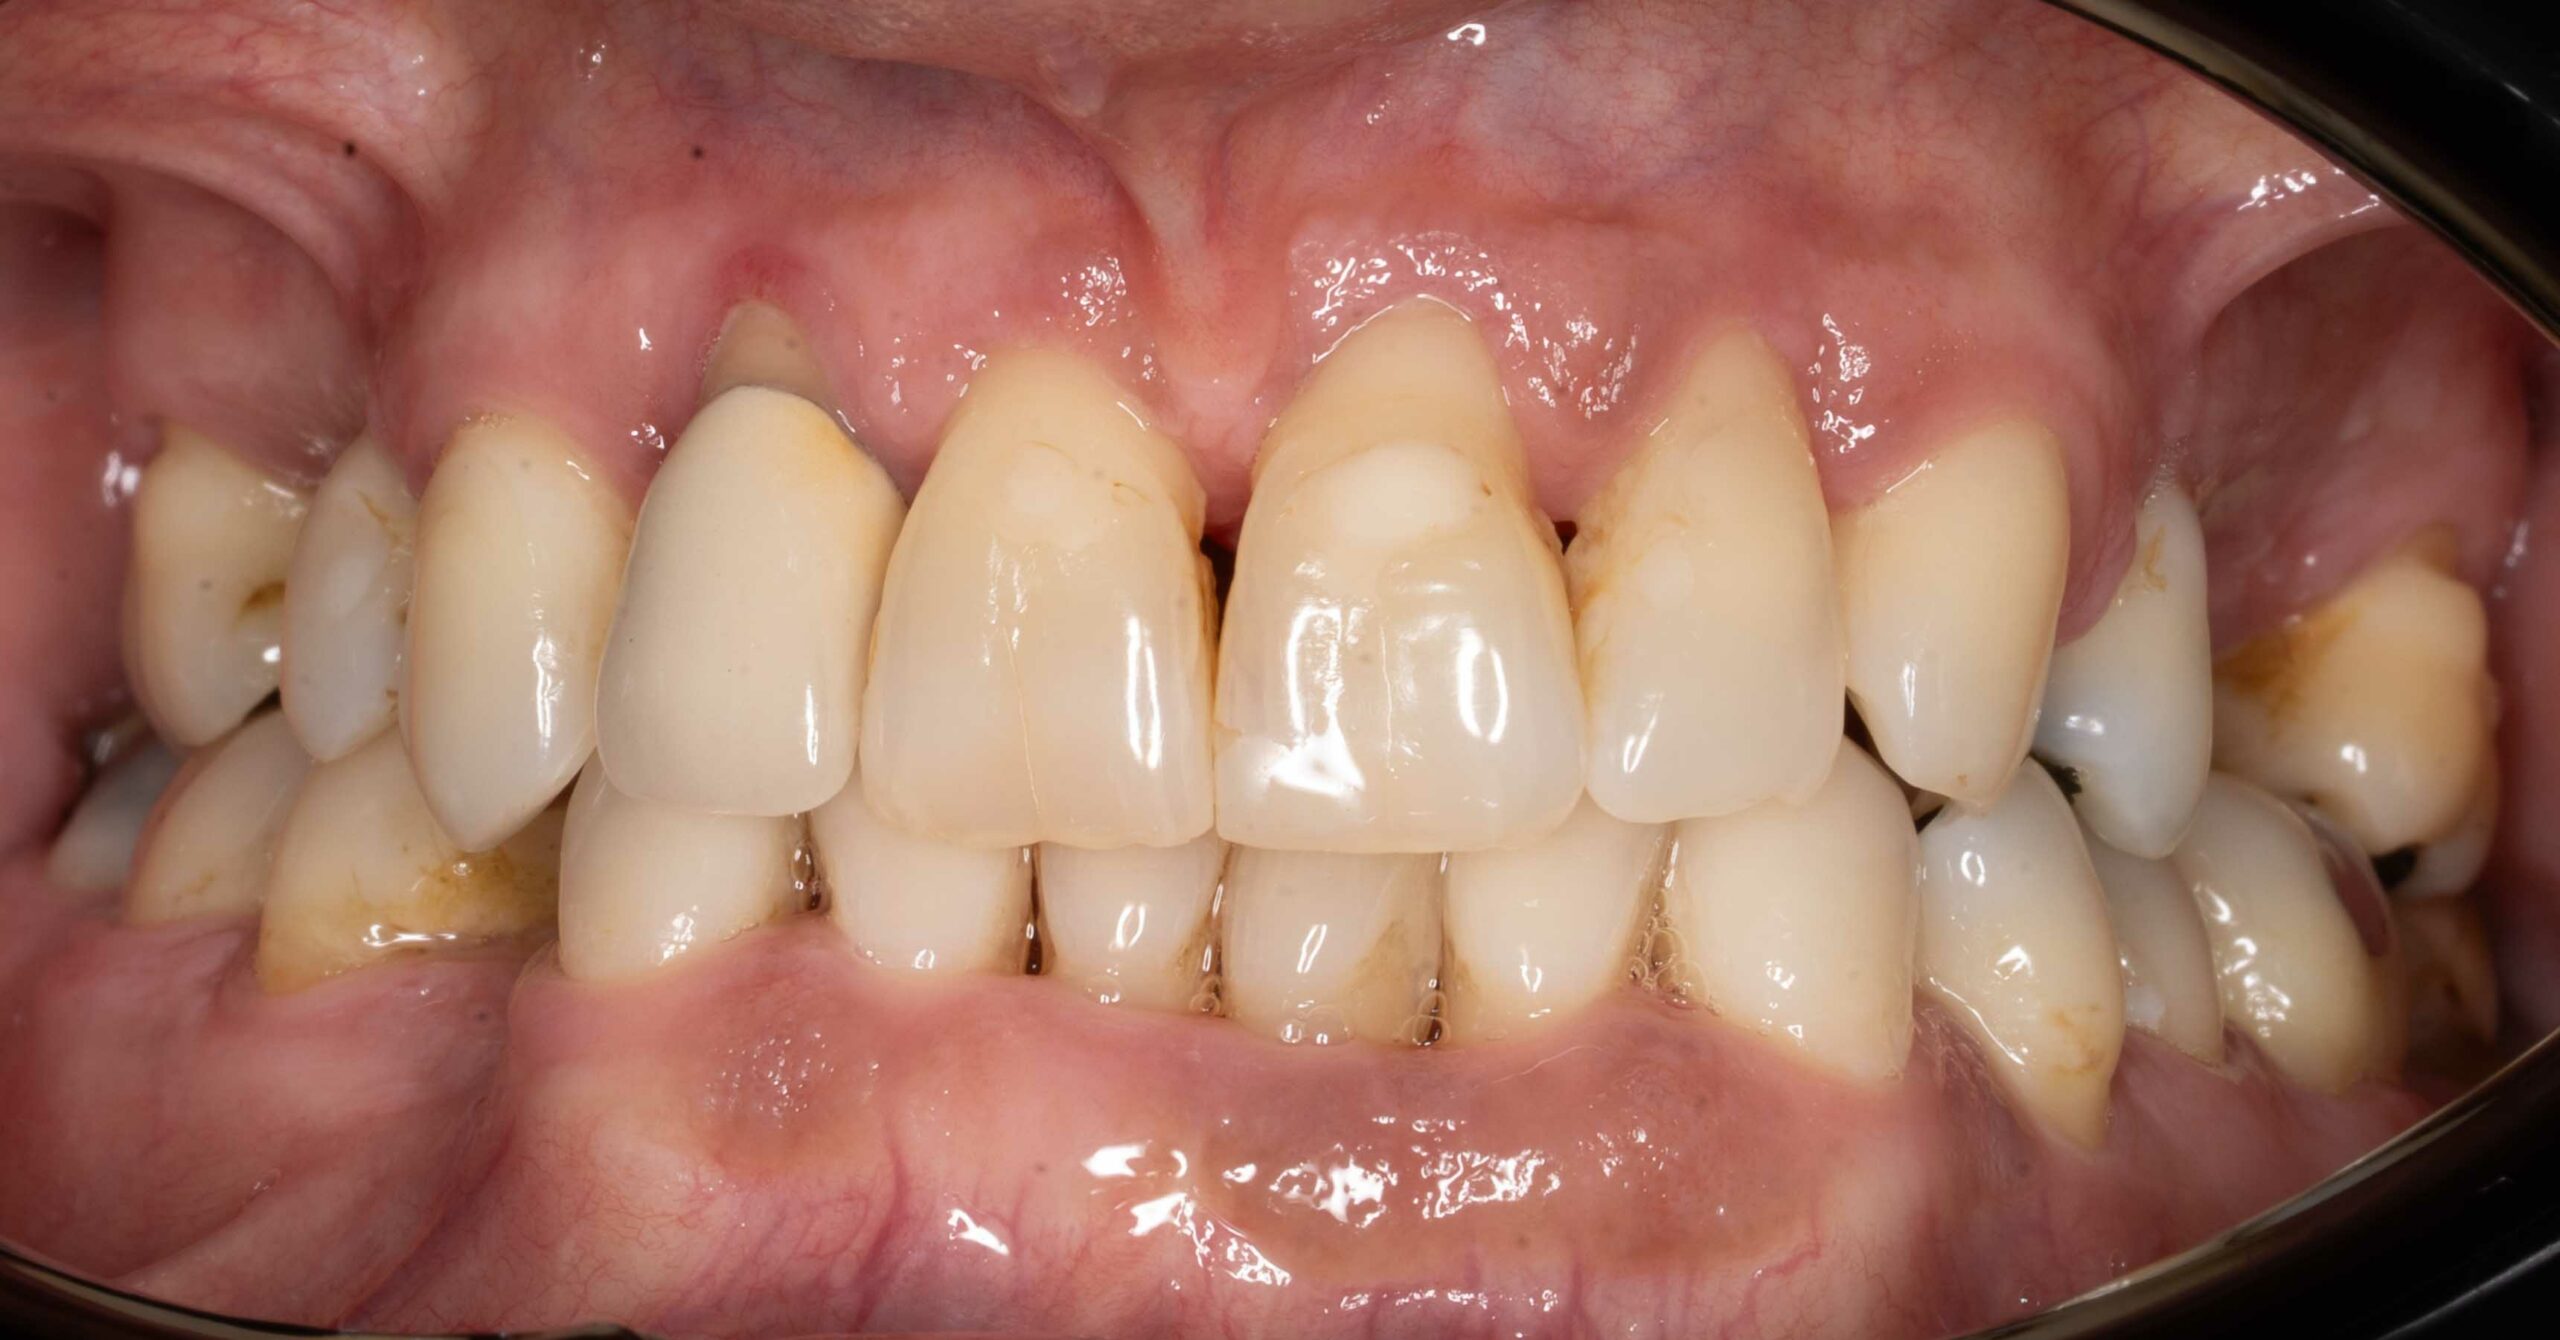

Pacjent zgłosił się z powodu licznych problemów z zębami oraz dolegliwości bólowych głowy. Zęby z powodu znacznej ruchomości nie stanowiły odpowiedniej podpory podczas żucia. Niestety wieloletniej terapia periodontologiczna choroby przyzębia nie przynosiła efektów. Zęby zostały zakwalifikowane do usunięcia. Nowy zgryz został odtworzony i oparty na 6 implantach w szczęce oraz 5 w żuchwie. Informacje z badania stawowe "kondylografii" pomogły zaplanować nowe prawidłowe zwarcie. Poza wyleczeniem dolegliwośći bólowych głowy oraz przywróceniu komfortu żucia i uśmiechu, Pacjent po zakończonej terapii zgłasza znaczne ograniczenie chrapania.

leczenie zaplanował oraz przeprowadził lek. dent Kamil Kikowicz